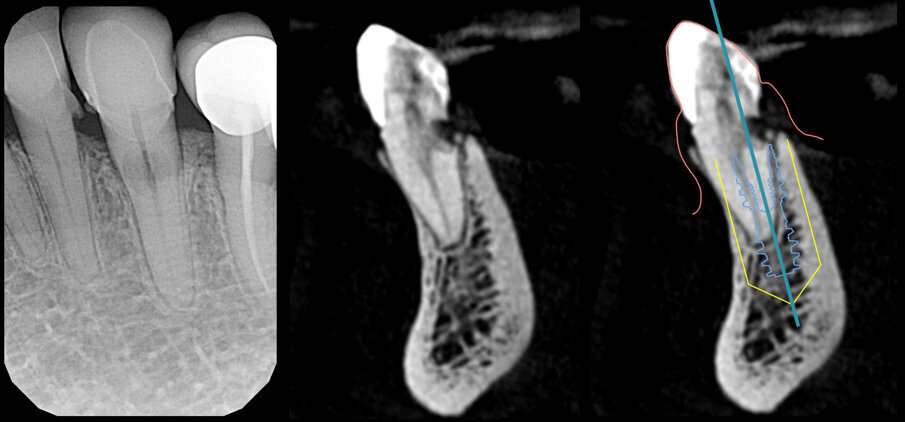

L’esame di primo livello (radiografia endorale) mostra la presenza di un minus dei tessuti calcificati a carico della radice. Si impone per ovvie ragioni un approfondimento volumetrico 3D: soltanto una CBCT ci consentirà di localizzare correttamente la lesione e valutarne la posizione, l’estensione e l’eventuale recuperabilità dell’elemento dentario. Il taglio trasversale della radiografia 3D mostra un riassorbimento radicolare esterno che riguarda la porzione linguale dell’elemento dentario (Figg. 1-4). Il riassorbimento presenta una posizione particolarmente sfavorevole, in quanto si estende già al di sotto del margine osseo crestale su un elemento dentario peraltro già trattato da un punto di vista protesico (Figg. 2, 3). Le opzioni terapeutiche proposte alla paziente sono sostanzialmente due: trattamento endodontico e rifacimento del restauro protesico, previo accesso chirurgico sul lato linguale con allungamento di corona clinica, oppure impianto post-estrattivo con tecnica Socket-Shield. La paziente sceglie questa seconda opzione e firma regolare consenso informato.

Fig. 4_Rx 2d e 3D, con evidenziazione del riassorbimento radicolare, che riguarda l’aspetto linguale e si approfondisce al di sotto del margine della corticale ossea; pianificazione implantare su apposito software di progettazione.